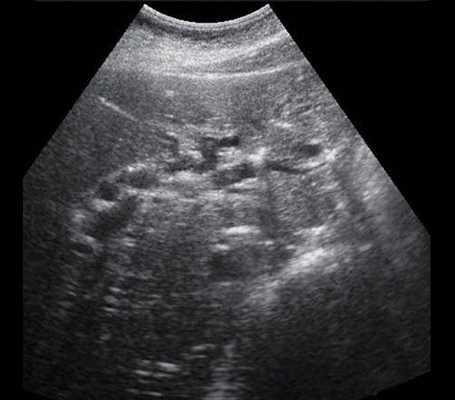

• УЗИ в черно-белом режиме

о Дилатация внутрипеченочных протоков

- Диаметр протоков > 2 мм

- Тубулярные анэхогенные ветвящиеся структуры, сопутствующие воротным венам:

Симптом «параллельного канала»

Зачастую самыми первыми из внутрипеченочных протоков расширяются протоки левой доли печени

- Расширенные протоки могут быть извитыми и иметь неравномерный просвет

- Проксимально у ворот печени сливающиеся тубулярные структуры формируют звездчатую структуру